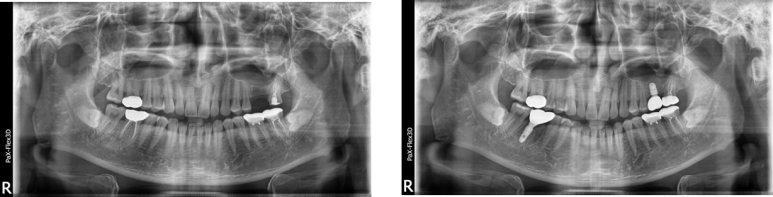

46세 여성

오른쪽 위 어금니 발치 후 뼈이식 진행하고 3개월 후 임플란트 식립

(전) 2021-07-16 (후) 2021-11-17

39세 남성

발치 및 임플란트 당일 식립 후 촬영한 엑스레이

(전), (후) 2022-02-17

38세 남성

(전), (후) 2022-02-05